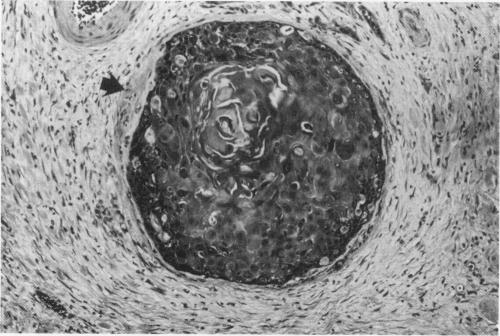

One hundred resected cases of squamous cell carcinomas of the oesophagus were reviewed and a series of histological criteria related to the survival time. Two histological features were important in the assessment of survival. Good prognostic factors were a marked lymphocytic response to the tumour and a lack of intravenous tumour infiltration. Presence of tumour in the middle third of the oesophagus, infiltration through the muscularis propria, severe tumour necrosis, glandular or small cell tumour differentiation, lymphatic invasion and lack of peritumoural fibrosis were all factors which tended to worsen prognosis. None of these factors reached statistical significance. The degree of squamous differentiation had no effect on survival.

回顾了100例食管鳞状细胞癌切除病例,并研究了一系列与生存时间相关的组织学标准。在评估生存情况时,有两个组织学特征很重要。良好的预后因素是对肿瘤有明显的淋巴细胞反应以及无肿瘤静脉浸润。肿瘤位于食管中段、浸润穿过固有肌层、严重肿瘤坏死、腺性或小细胞肿瘤分化、淋巴浸润以及无肿瘤周围纤维化都是倾向于使预后恶化的因素。这些因素均未达到统计学意义。鳞状分化程度对生存无影响。